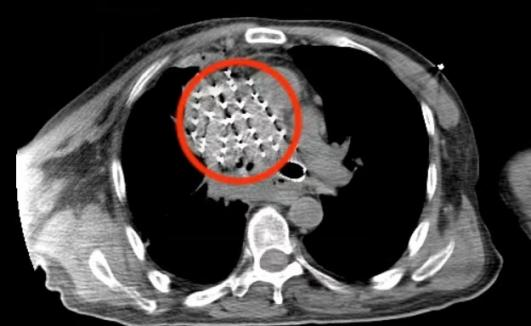

圖片

CT下碘125粒子植入